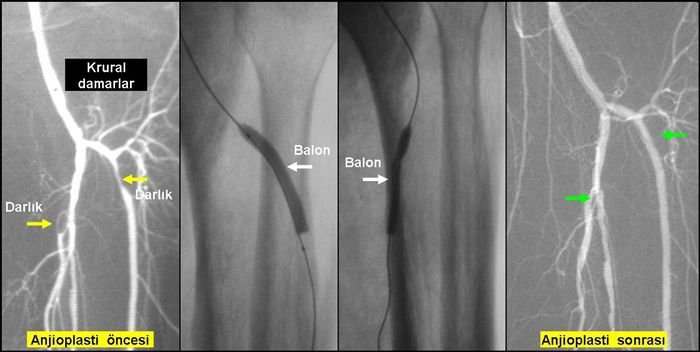

Hastaya aynı gün mr angıo dediğimiz veya normal kasıktan angıo yoluyla darlık tesbit edilip diz üstü darlıklara stent ve balon,diz altınaysa özel ilaç kaplı balonlarla müdahele etmekteğiz. 1 gün sonrada hasta belli kan sulandırıcı tedavi önerisiyle taburcu edilmektedir.